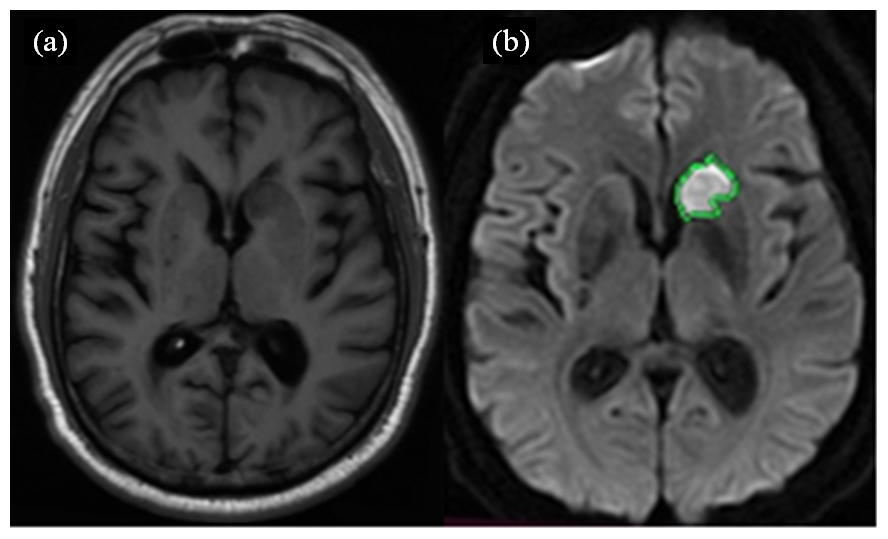

| 图4 磁共振轴位SE T1WI图像(a)、DWI图像及病灶最大层面面积测量示意图(b). (a)中,左侧尾状核头部区急性梗塞病灶, 呈长T1信号;(b)中,DWI扩散受限呈高信号 |

| Fig. 4 Magnetic resonance axial SE T1WI (a), DWI and the schematic diagram of the maximum lesion area measurement at the largest layer (b). In (a), MRI showed an acute infarction lesion in the head of the left caudate nucleus, presenting as long T1 signals; In (b), DWI showed restricted diffusion with high signal intensity. |